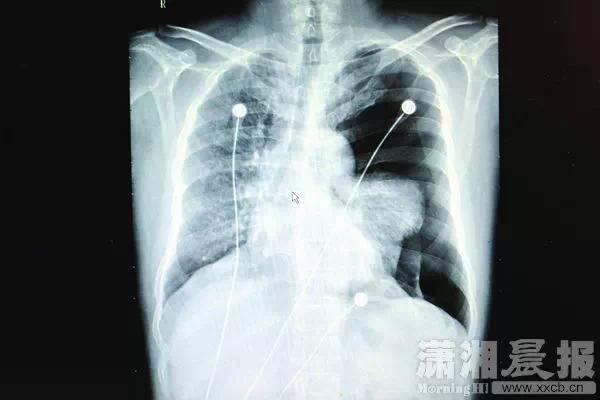

◆2015年1月的一天,湖南长沙喜欢“飙高音”的李先生和朋友在KTV唱到凌晨才回家。

当晚李先生感觉胸口不适,以为是自己喝多了酒,并未在意。第二天早上,李先生像往常一样到小区花园散步,胸口出现针刺一样的痛感,家人急忙把他送到医院。经开胸手术后才保住性命。

专家诊断,是肺大疱破裂引发了气胸。

“患者入院时呼吸、讲话都很困难,检查发现其左肺已压缩了60%以上,心脏已受压移位,若不及时处理,很可能会危及生命。”医生说。